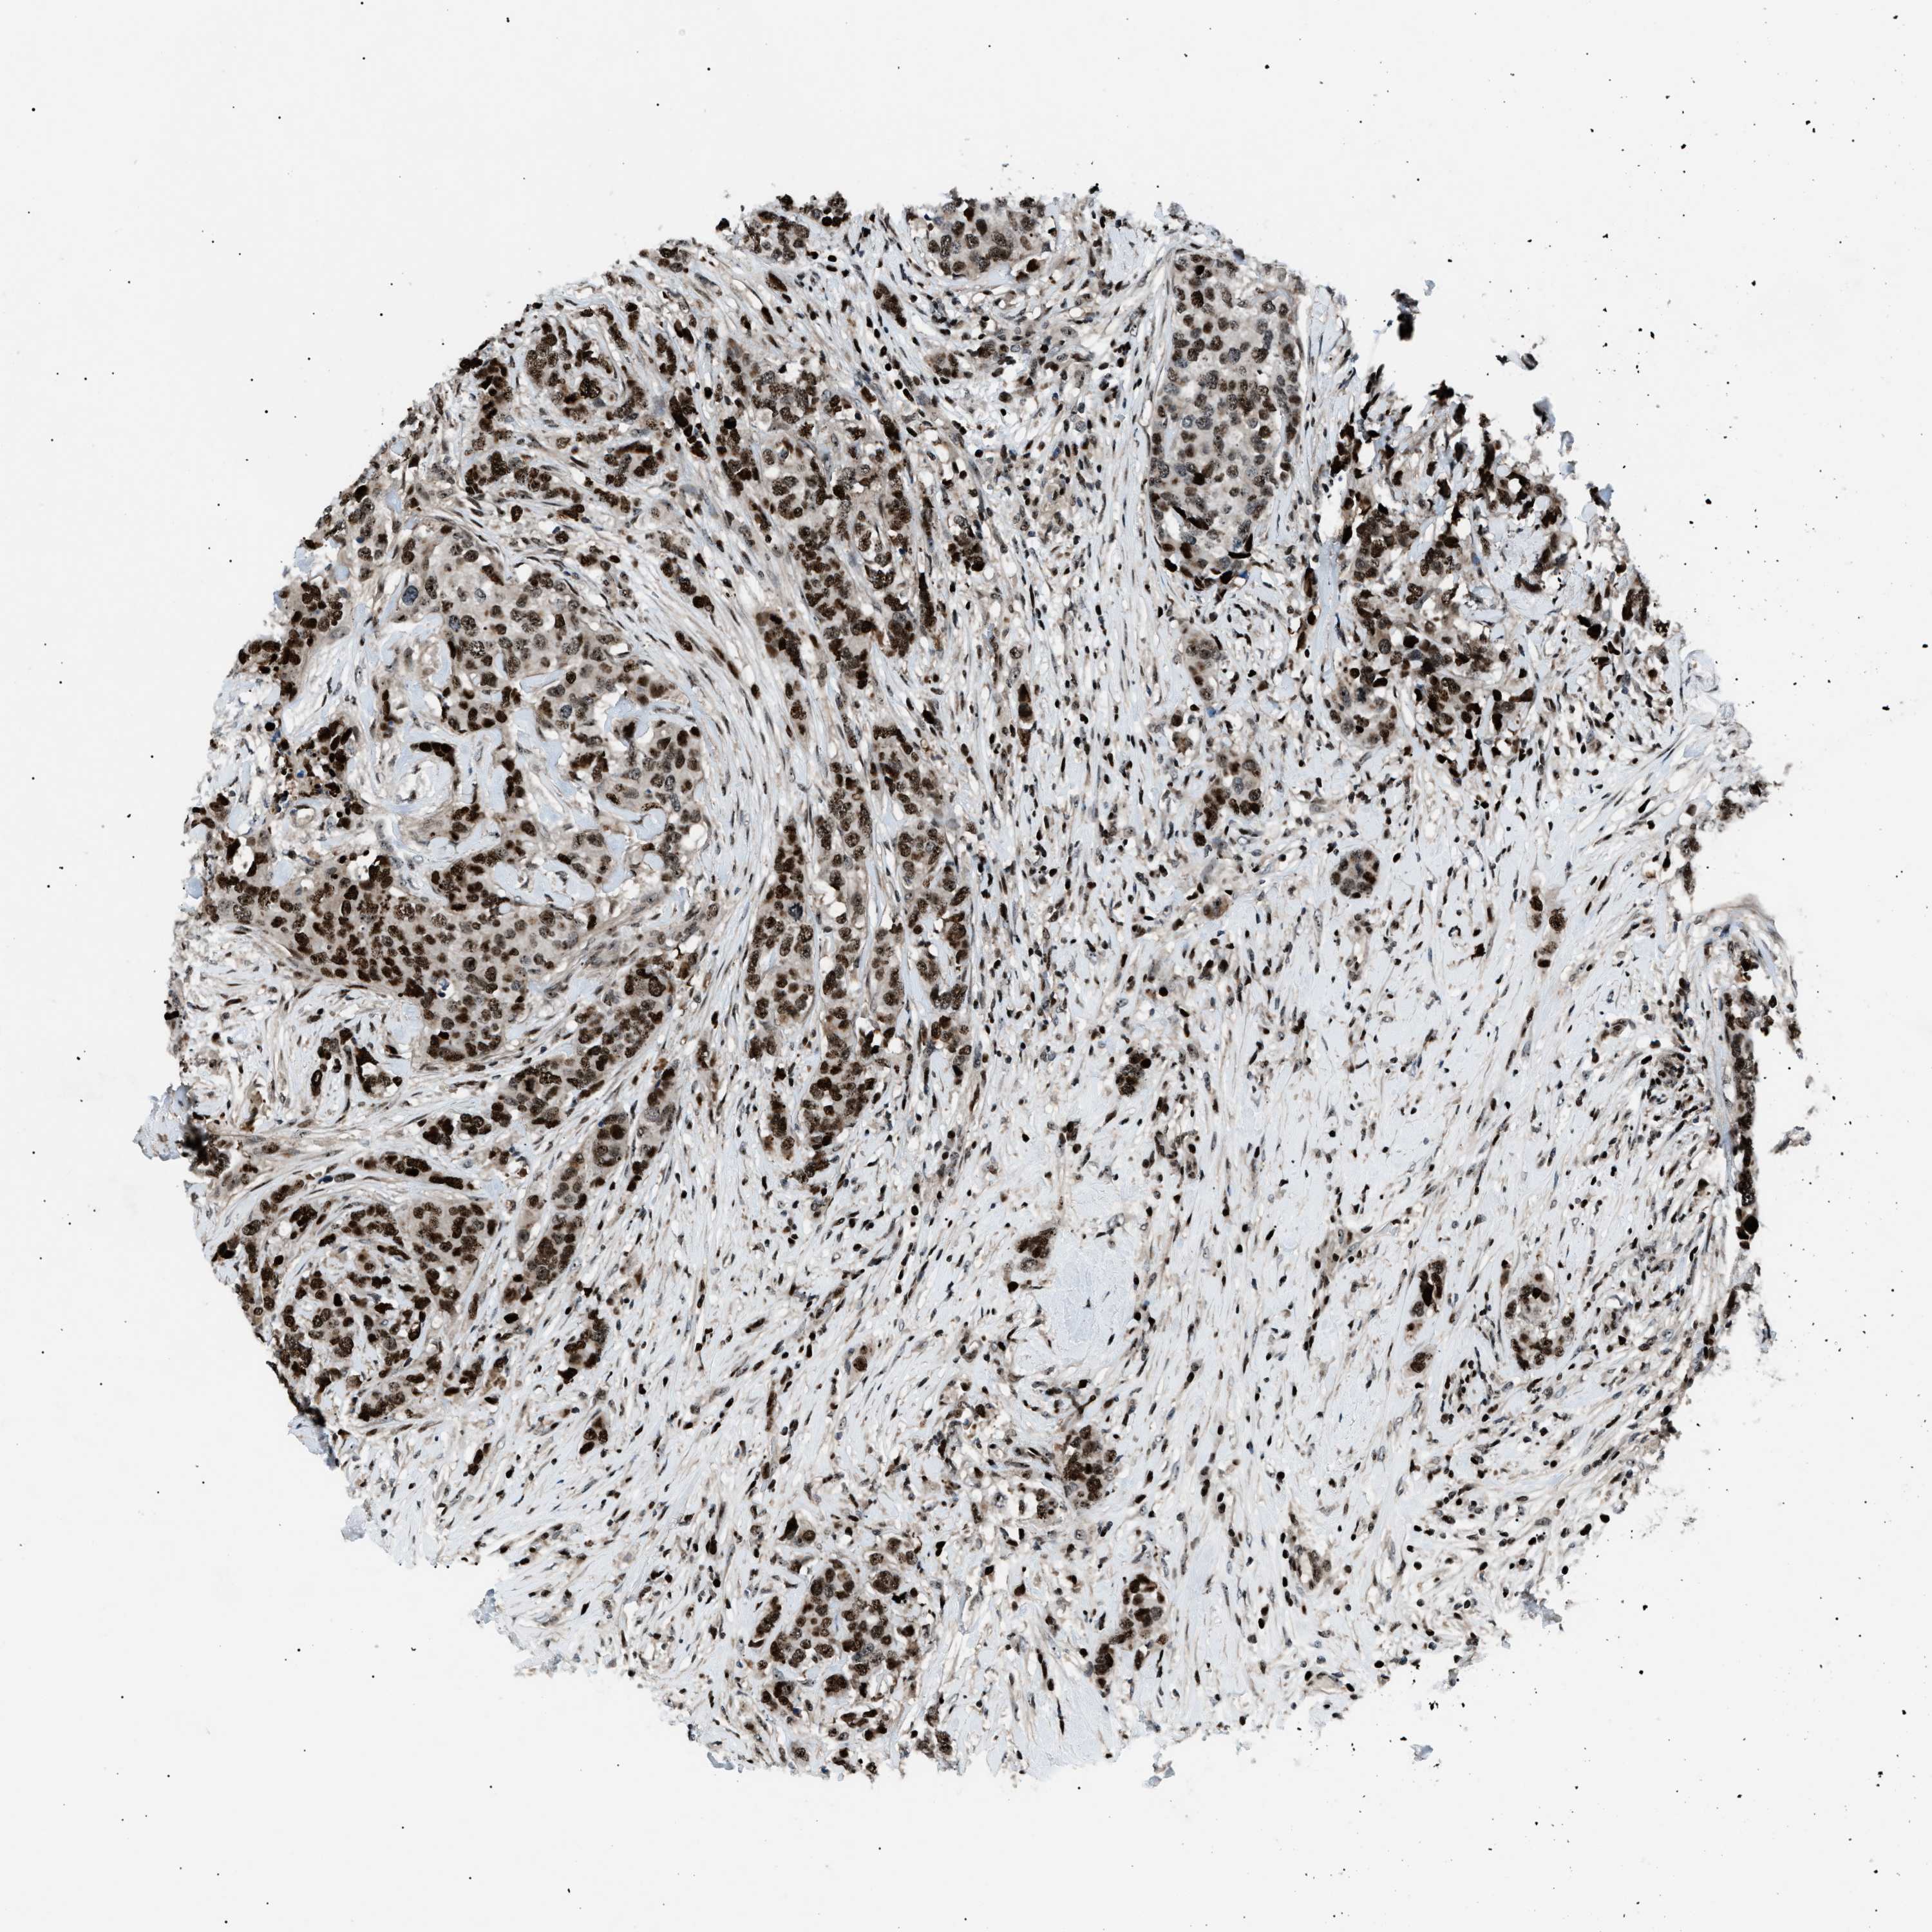

CANCER BREAST CANCER Show tissue menu

BRCA TCGA BRCA VALIDATION PROTEIN EXPRESSION

Breast cancer

Human cancer

Breast invasive carcinoma

PRKX is not prognostic in Breast Invasive Carcinoma (TCGA)